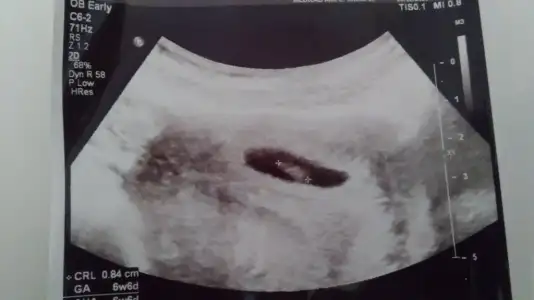

Teşekkür ederimm. Doktor bugün kız gibi duruyor dedi ama net bir şey söylemedi bacağıyla kapattı. Ben de erkek olduğunu düşünüyorum baştan beri öyle hissediyorumErkek olma ihtimali çok yüksek bence

Kız görünüyor

Haydi bakalım canim, herkes kiz dedi. Sen erkek. Son durumu paylaşacağım.Erkek gibi sanki